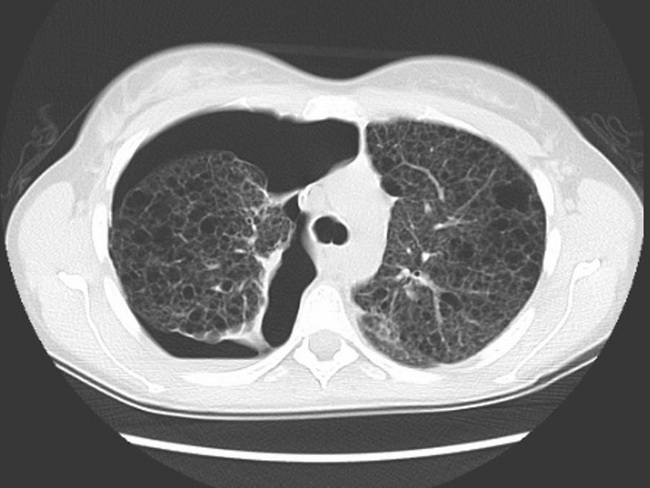

Визуализация и диагностика неинвазивного аспергиллеза с помощью КТ

Раздел: Необычные решения